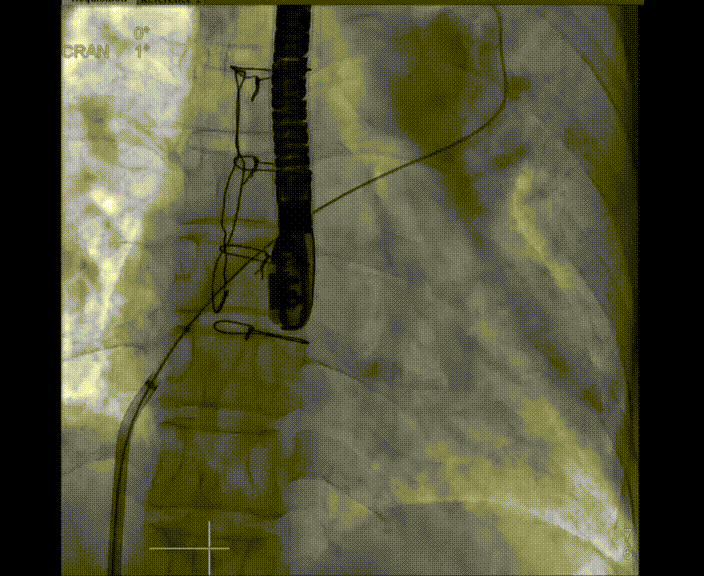

術(shù)中首先在局麻下穿刺股動脈、股靜脈,完成心導(dǎo)管檢查評估后轉(zhuǎn)為全麻,在食道超聲引導(dǎo)下穿刺房間隔,穿刺成功后將加硬導(dǎo)絲送入左上肺靜脈建立軌道,根據(jù)患者病情行球囊預(yù)擴張后植入6mm孔徑房間隔造孔支架,經(jīng)透視及食道超聲評估支架左右盤展開良好,夾持于房間隔兩側(cè),固定穩(wěn)定、位置良好,食道彩超顯示房水平右向左為主分流,分流孔直徑符合預(yù)期大小,心導(dǎo)管檢查評估達到預(yù)期效果,釋放造孔支架。術(shù)后12h患者下床活動,恢復(fù)順利,擬于近日完善術(shù)后評估后出院。